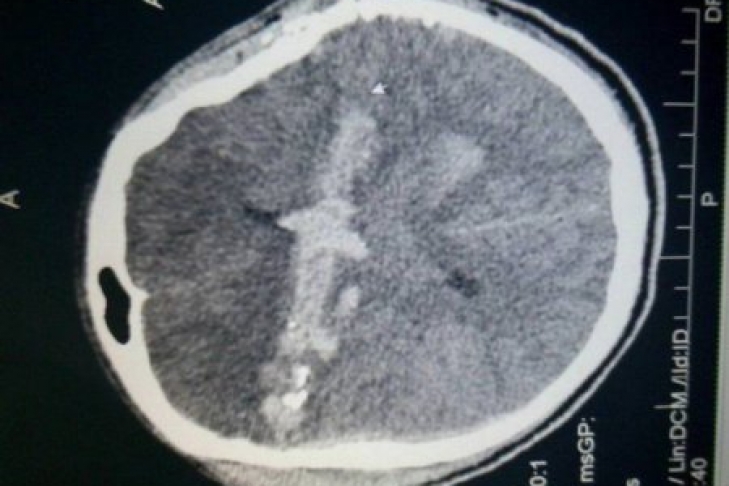

"Иван, 26 лет, из Закарпатской области Виноградовского района получил ранения возле поселка Новотроицкое. Пуля вошла в правую лобную область и вышла в височную слева. Кома. Искусственная вентиляция легких. Военные доставили прямо в реанимационный зал больницы Мечникова. Тяжелая нейрохирургическая операция с удалением мозгового детрита, костных обломков. Утром у Ивана появилось движение в конечностях. Появилась надежда на его спасение", - пишет Рыженко.